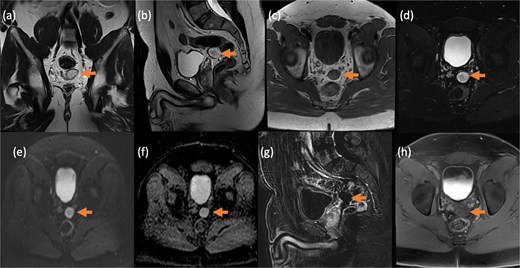

Pelvic magnetic resonance imaging (MRI) further characterized the pelvic lesion as a well-defined, non-enhancing, fluid-filled cyst measuring 3 × 2 × 1 cm without solid components, raising suspicion for pelvic hydatid seeding, although peritoneal inclusion cyst was also considered (Fig. 3). A 99mTc-dimercaptosuccinic acid (DMSA) scan showed preserved renal function with the right kidney contributing 25.7% of total function and a photopenic defect at the cyst site (Fig. 4). No other lesions were found on chest CT or brain MRI. Colonoscopy ruled out malignancy but revealed incidental low-grade adenomas.

Contrast-enhanced MRI of the pelvis in different sequences and different planes demonstrates a small, well-defined, oval-shaped lesion with high signal intensity on T2-weighted images (bold arrow—a and b) and low signal intensity on T1-weighted images (bold arrow—c). The lesion is located in the pelvis, inseparable from the seminal vesicles and the anterior rectal wall. It shows no signal drop on fat-saturated T2 sequence (bold arrow—d) no signify macroscopic fat, no restricted diffusion (dashed arrow—e and f) with T2 shine through, and no post-contrast enhancement on early subtracted (arrow head—g) and no delayed enhancement (arrow head—h). No solid component.

Renal hydatid disease presents diagnostic challenges due to its rarity and often non-specific symptoms. In this case, serological tests were negative—a known limitation in isolated renal hydatid disease due to low sensitivity in localized infections [3]. Imaging played a pivotal role in diagnosis and surveillance. CT confirmed cystic recurrence, and MRI was essential in evaluating the pelvic lesion. Although rare, pelvic seeding may result from intraoperative spillage or rupture [2]. In our patient, the pelvic lesion was managed conservatively with serial imaging, as its stability and benign features supported observation rather than intervention.

MRI findings—high T2 signal, absence of enhancement, and lack of diffusion restriction—suggested a benign cyst. Yet, the patient’s surgical history warranted suspicion for secondary hydatid dissemination. This highlights MRI’s value in soft tissue evaluation where CT may be limited [5].